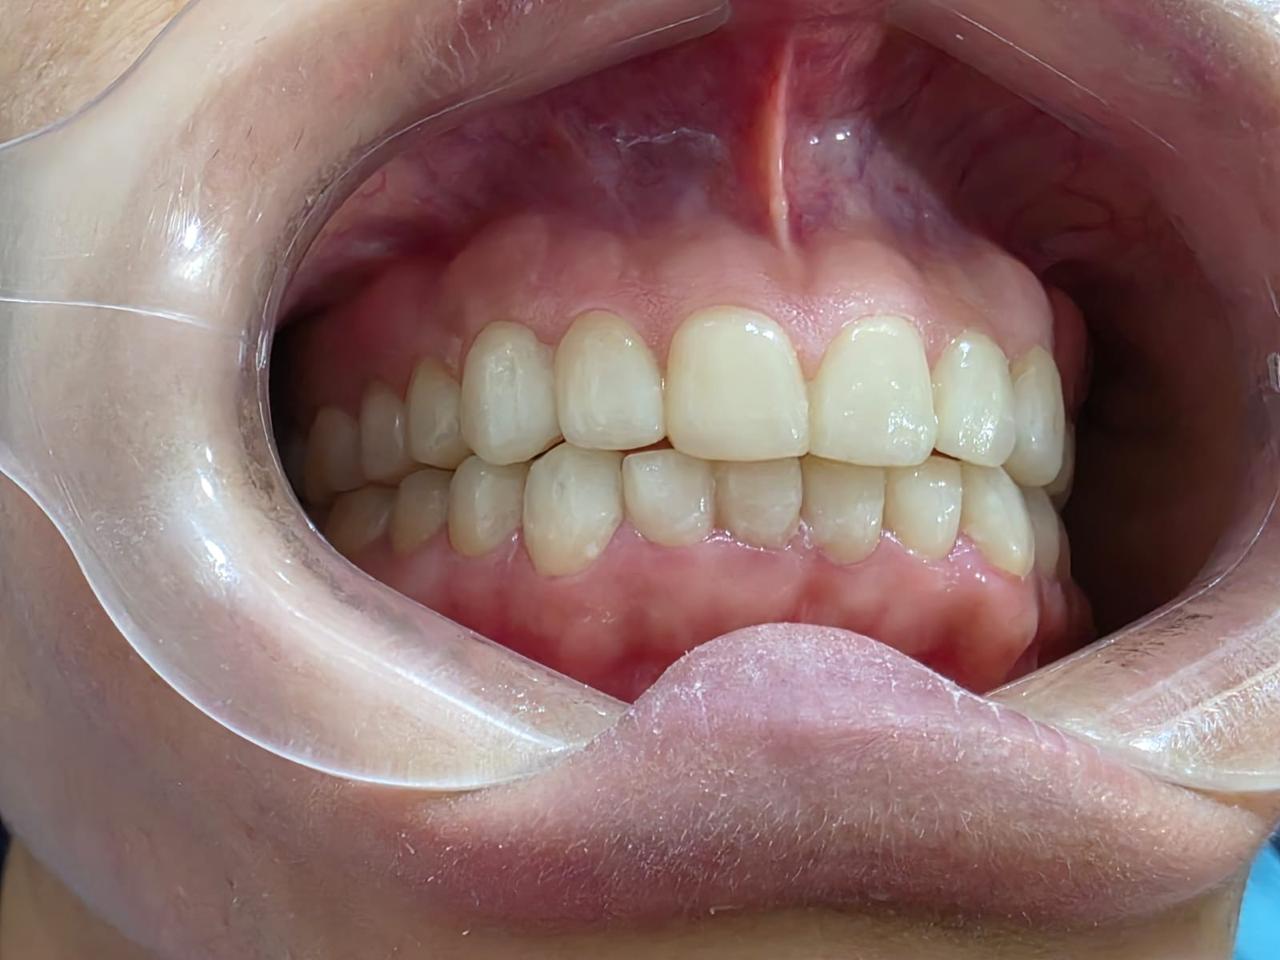

Our Crowns and Bridges service provides strong, long-lasting solutions for repairing damaged teeth and replacing missing ones. Dental crowns are custom-made caps placed over weakened or fractured teeth to restore their shape, strength, and natural appearance. Bridges are used to fill gaps caused by missing teeth, helping to maintain proper bite, prevent shifting, and enhance your smile’s aesthetics. Using high-quality materials such as ceramic, porcelain, zirconia, and metal, we ensure each restoration blends seamlessly with your natural teeth. Our skilled team uses advanced digital technology for precise fittings, improved comfort, and long-term durability. Whether you need protection for a single tooth or a complete bridging solution, our crowns and bridges restore full function and beauty to your smile.